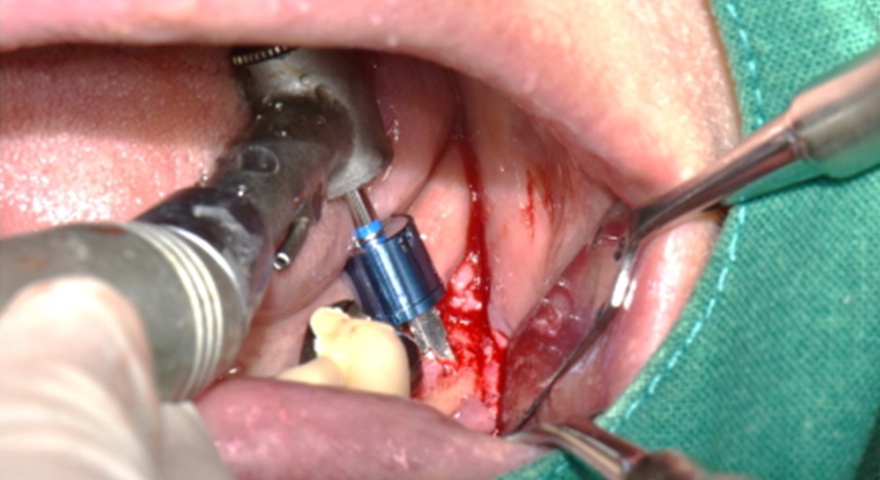

Після проведення стандартної імплантації в ділянках з оголеною різьбою було застосовано техніку DUK: на імплантат наносили спочатку пастоподібний матеріал, далі — гранули, після чого укладали мембрану та закривали клапті швами без натягу. Всі пацієнти отримували антибіотики (амоксицилін) та знеболення (ібупрофен), а через шість місяців — проходили контроль та біопсію ділянки.

Рис. 2. (A) Пацієнт із виявленою необмеженою (non-contained) втратою кісткової тканини та оголенням імплантату з букального боку на момент встановлення імплантату. (B) Нанесення основного шару пастоподібного кісткового матеріалу перед внесенням гранульованого кісткового трансплантата. (C) Укладання колагенової мембрани з покриттям зони трансплантації — від букального до піднебінного боку — та фіксували за допомогою внутрішніх періостальних швів. (D) Через шість місяців після аугментації — візуалізується регенерація кістки з букального боку в ділянці раніше оголеної різьби імплантату.